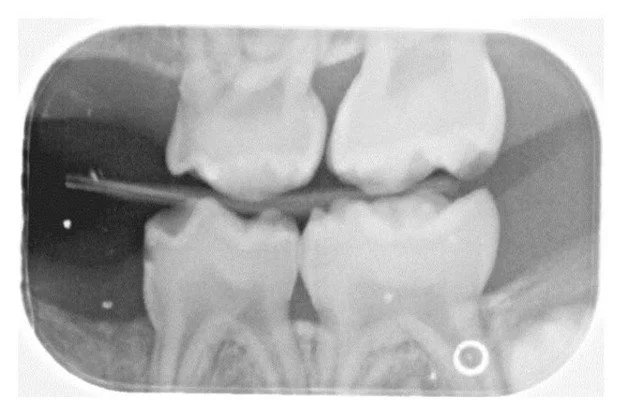

Radiographs confirmed what clinically appeared to be the complete absence of the maxillary left and mandibular right primary canines (63 and 83). Additionally, the right bitewing radiograph showed a suspicious area mesial to the maxillary right first primary molar (Figure 2). A follow-up periapical radiograph of this region was obtained, which demonstrated an unerupted dysmorphic maxillary right primary canine tooth (53) positioned ectopically near the mesial aspect of the maxillary right first primary molar (Figure 3). Upper right and lower left periapical films have atypical presentation distal to the upper right lateral permanent incisors and between permanent lower left canines and lateral incisors. It appears that the tribal leader failed to completely extirpate the developing upper right maxillary primary canine (53), and probably the lower left primary canine (73) due to the continued development of the upper right maxillary primary canine (53) and what appears to be a developing tooth-like remnant on the lower left primary canine area (73) (Figure 4). Additional radiographs confirmed the absence of the maxillary and mandibular left primary canines (Figures 5 and 6). These areas will be followed for the possible formation of supernumerary teeth or odontomas.

Figure 2

The right bitewing radiograph shows a suspicious area mesial to the maxillary right first primary molar. Caries are noted on the distal surface of the mandibular right first primary molar.

Caries were also noted on the mandibular left first primary molar and the mandibular right first primary molar (Figure 2). All findings and a treatment plan to restore the carious lesions were presented to the caregiver. Regarding the missing primary canines, an orthodontic plan was developed to follow the patient's growth and development and refer the patient to an orthodontist for evaluation at age seven. The permanent canines, lateral incisors, and first premolars will be monitored for possible hypoplasia secondary to trauma caused by the extirpation of the primary canines.